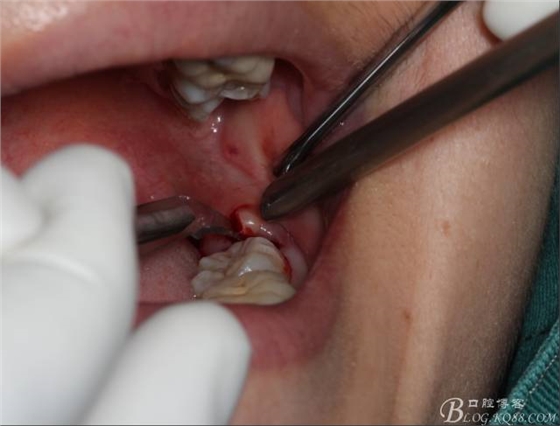

切開:角形切口,這個位置切開我喜歡更易操作12#刀。

鈍性翻辨露冠

角度鍋輪機結(jié)合冷鹽水冷卻分冠

分冠完成

取出阻力部分冠

在取出阻力冠后,嘗試性看能取出全部的牙體不,就是取不出也能整體撬動牙根。

計劃總趕不上變化,何況是充滿變異的智齒。由于可操作空間較小,原來計劃橫向分根改成矢狀分根。

現(xiàn)在都在提倡微創(chuàng),個人看法微創(chuàng)是相對,所當然微創(chuàng)是我們的追求。完全撥出,縫合關閉創(chuàng)口,常規(guī)智齒撥除醫(yī)囑,不適隨診。